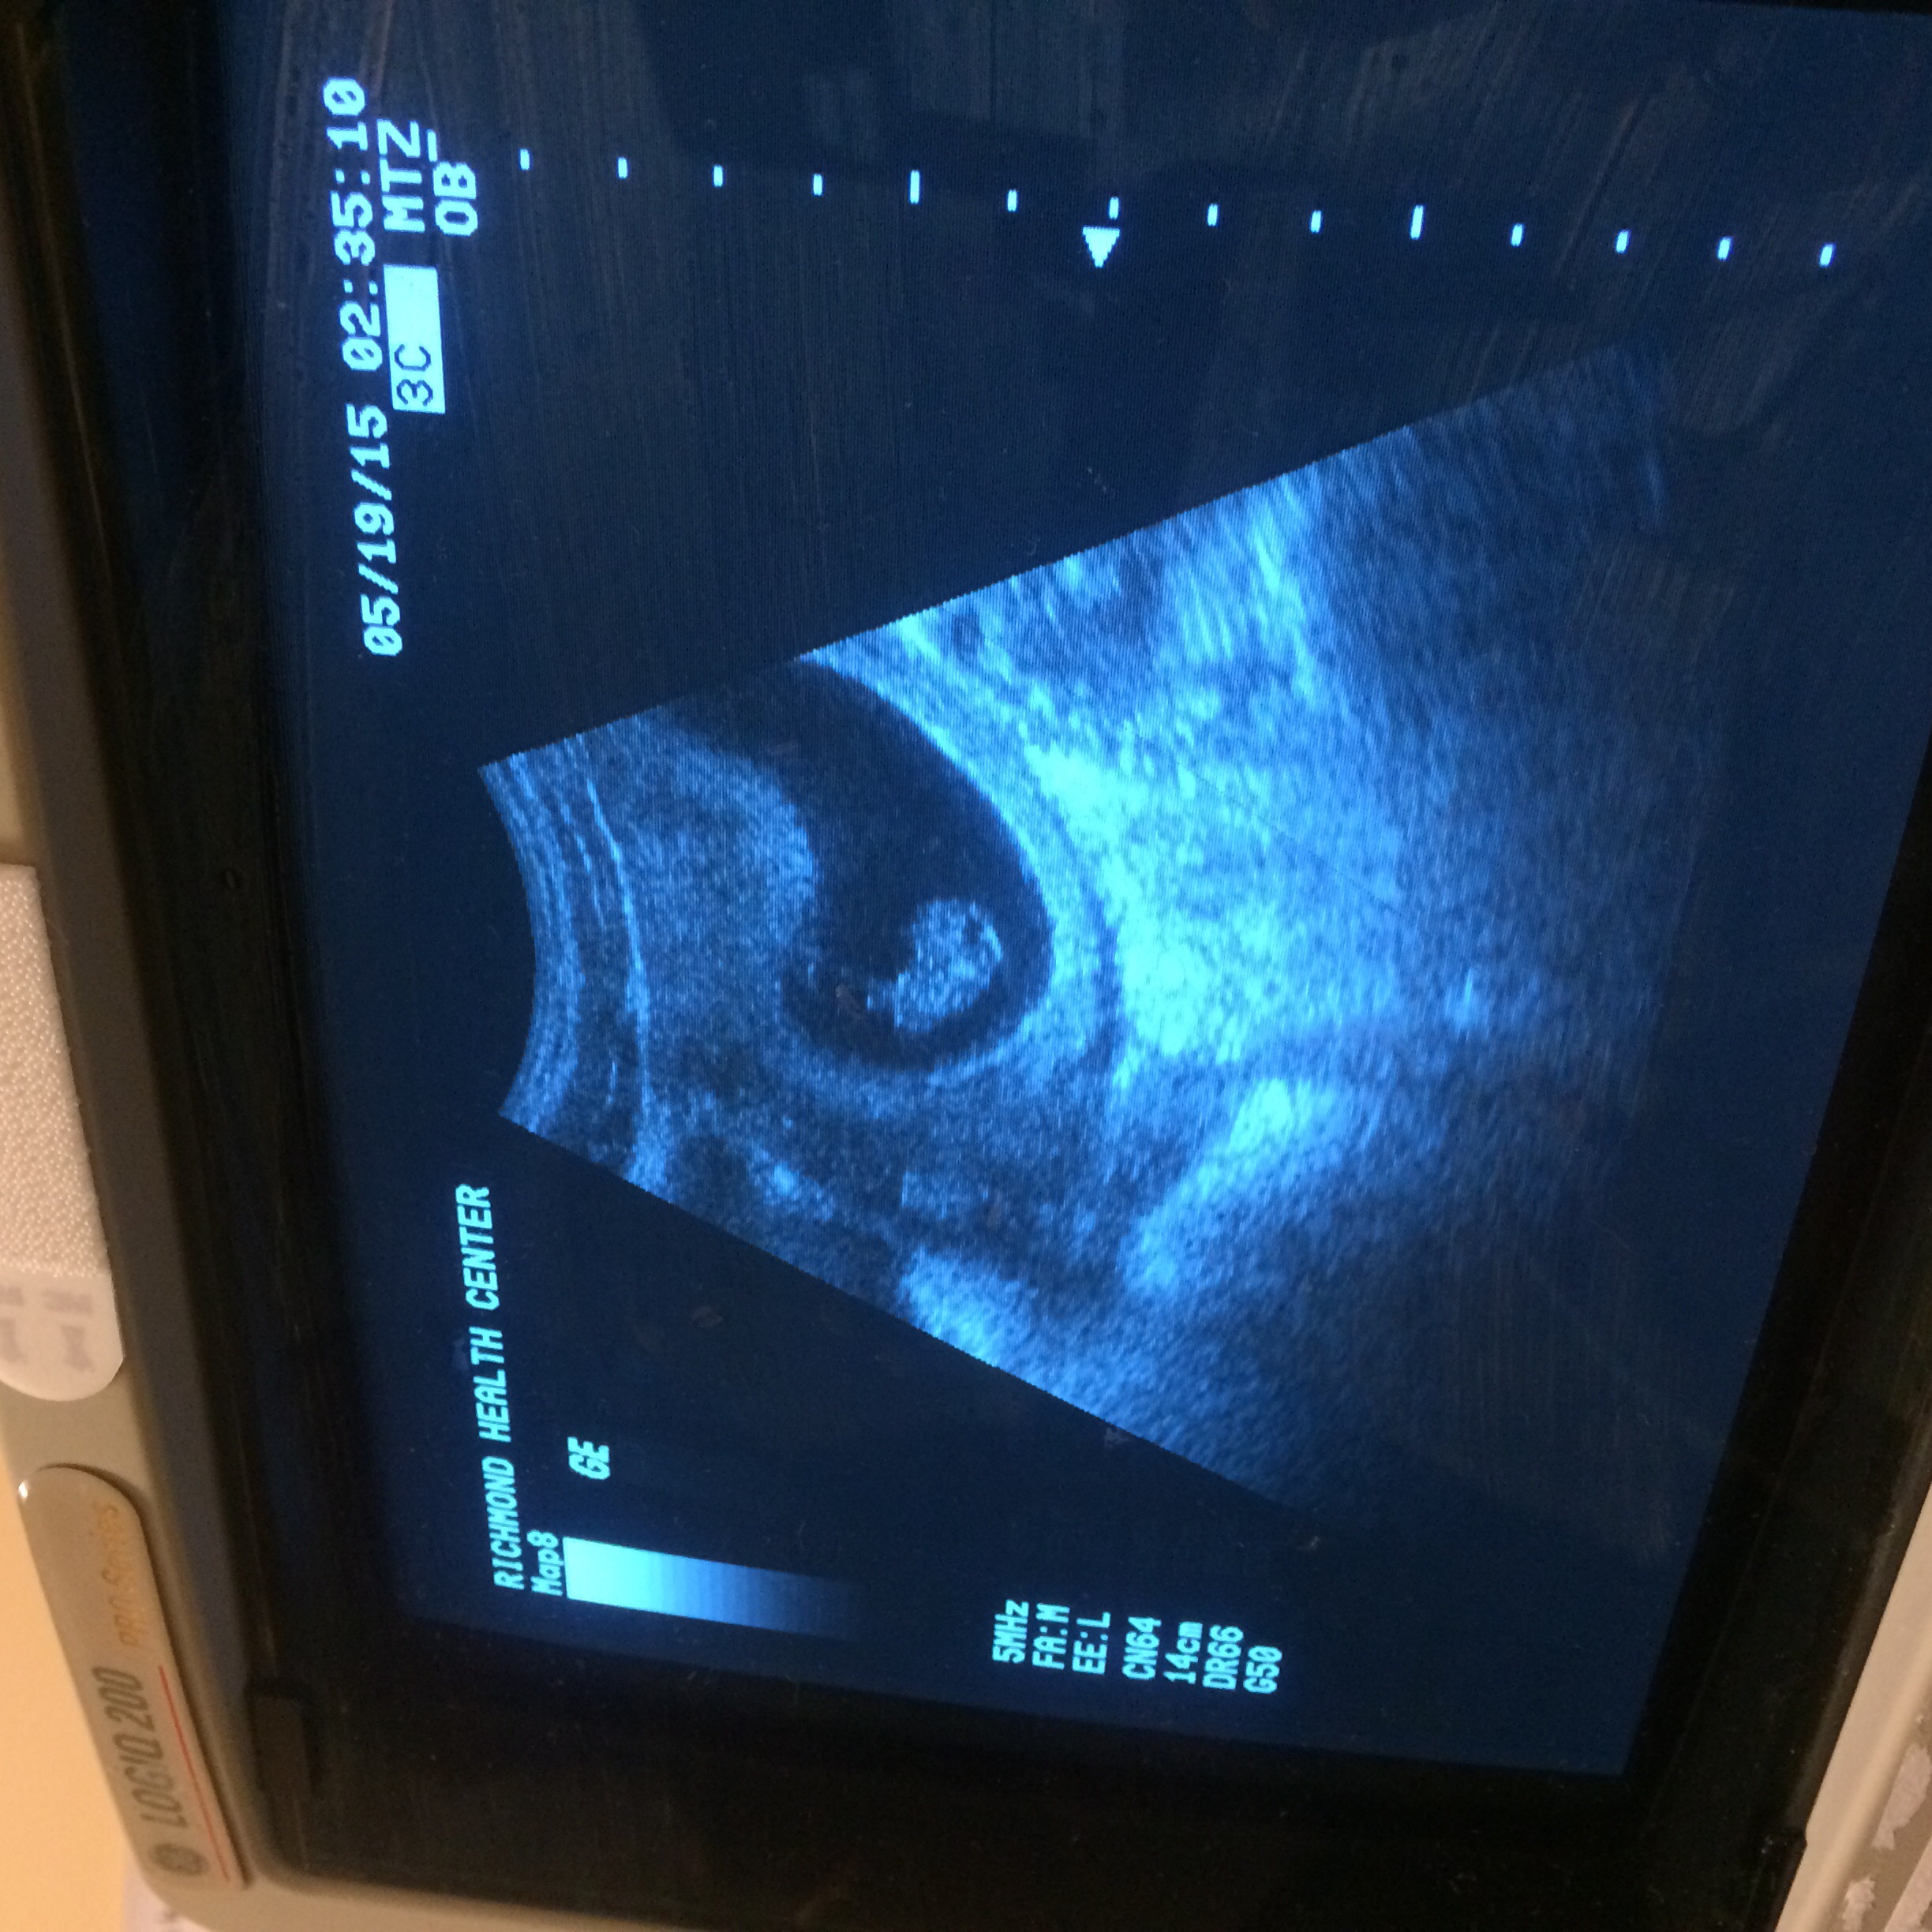

U/S is somewhat hard to see but head on left and arm bud sticking up, waving hi :-h Hi buddy!

Edit: oops, sideways pic confusion